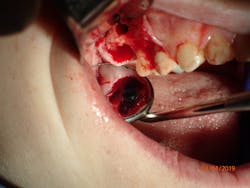

Therefore, if a patient has 5 mm of available bone height from the sinus floor, a maximum of 5 mm is prudent to expect from an indirect lift; therefore, an 8 mm to 10 mm implant is the ideal choice. The tapered iHex or MorsTorq implant provides safety when dealing with sinus areas, for three reasons. First, the taper helps prevent overinsertion toward the sinus cavity. Second, the abutment and transfer attached to the implant allows for more control. Finally, the rounded apex helps reflect the sinus floor without creating damage (figures 1-6).